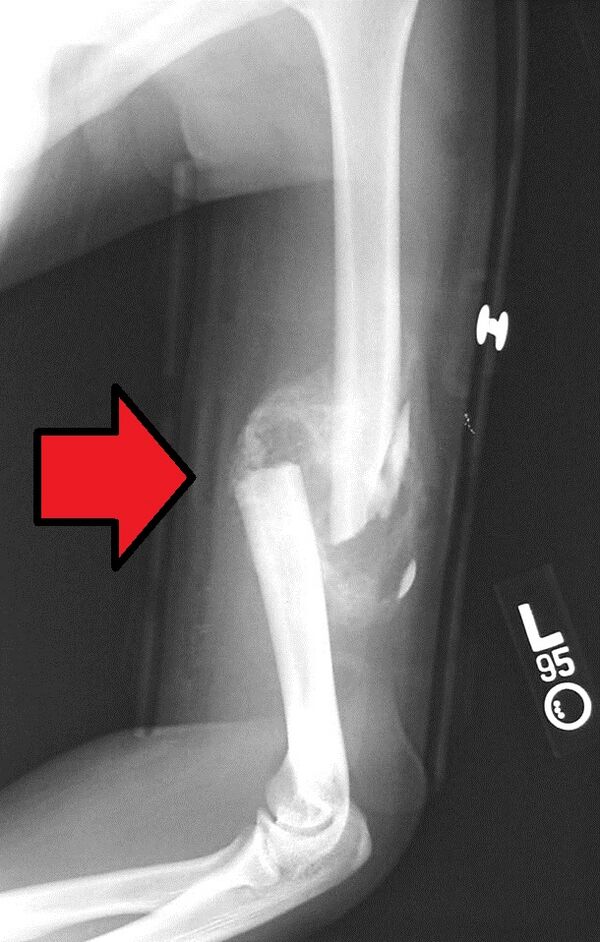

Вначале образуется соединительнотканная провизорная мозоль, к концу первой недели образуется остеоидная ткань, которая превращается либо непосредственно в костную, либо сначала в хрящевую, а затем в костную. Мозоль возникает из костеобразующих клеток надкостницы и эндоста. Образование костной мозоли играет важную роль в процессе срастания поврежденной кости. Костная мозоль, представляющая на рентгенограмме слегка затемненную область, в конце концов кальцифицируется и моделируется.